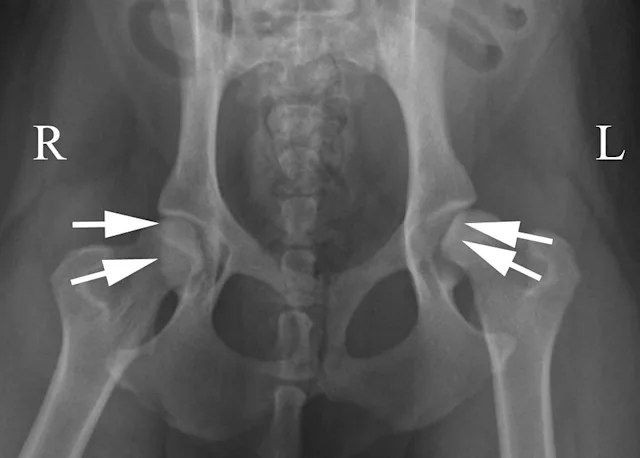

A radiograph displays a dog's pelvis, with clear indications of the left and right sides labeled. Arrows point to the hip joints, highlighting signs of hip dysplasia, characterized by abnormal joint spacing and alignment.

The ventrodorsal radiograph with the legs lying in a neutral to flexed position is often called the "frog-legged" position. This view is particularly useful in cases of pelvic trauma because minimal stress is placed on the pelvis and coxofemoral joints. The dog is placed in dorsal recumbency in a foam positioning trough and the limbs are not held. It is still important to maintain symmetry of the pelvis and limbs. Figure 5A demonstrates a dog positioned for this view. Figure 5B shows an example of this positioning in a cat with bilateral capital physeal fractures (white arrows).